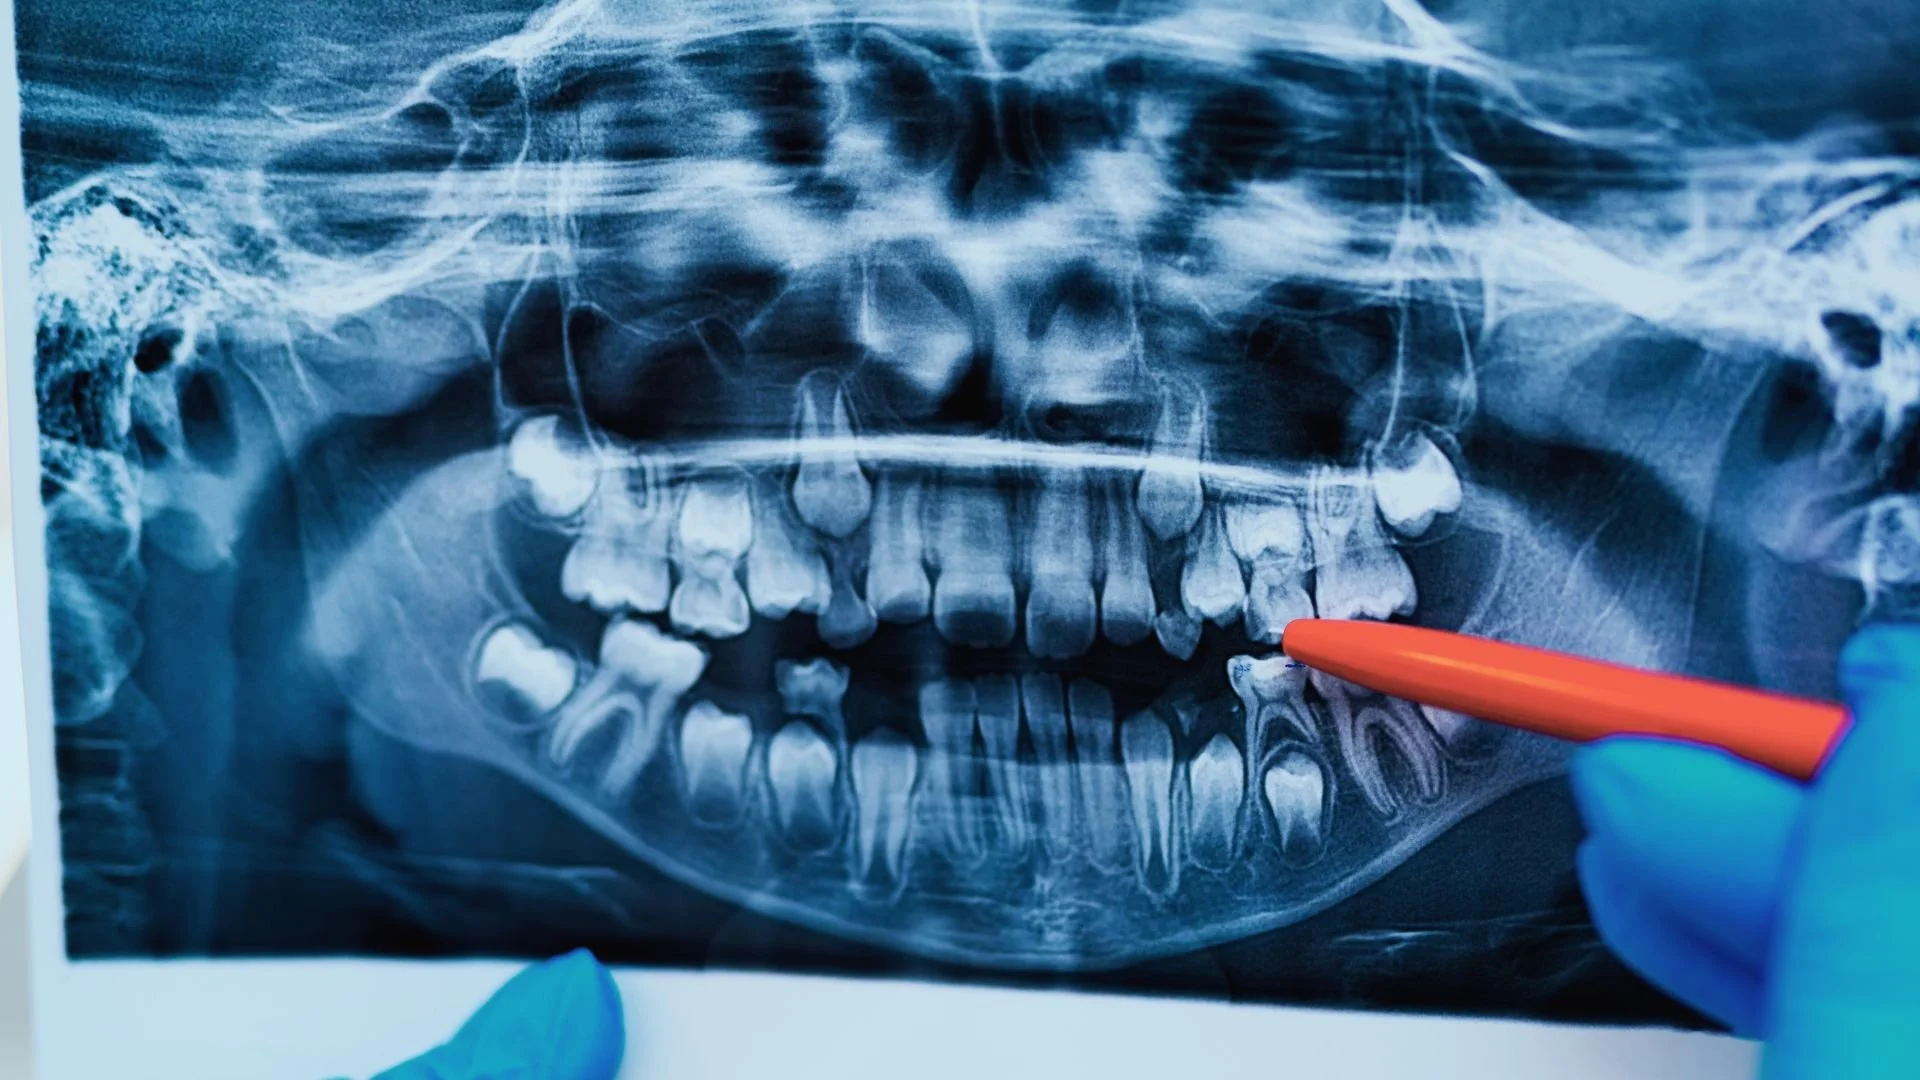

Tooth Extraction x Ray